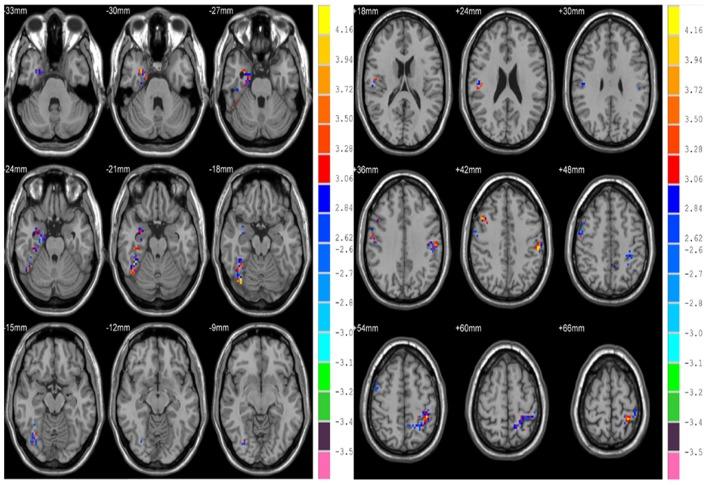

Exploring functional information among various brain regions across time enables understanding of healthy aging process and holds great promise for age-related brain disease diagnosis. This paper proposed a method to explore fractal complexity of the resting-state functional magnetic resonance imaging (rs-fMRI) signal in the human brain across the adult lifespan using Hurst exponent (HE). We took advantage of the examined rs-fMRI data from 116 adults 19 to 85 years of age (44.3 ± 19.4 years, 49 females) from NKI/Rockland sample. Region-wise and voxel-wise analyses were performed to investigate the effects of age, gender, and their interaction on complexity. In region-wise analysis, we found that the healthy aging is accompanied by a loss of complexity in frontal and parietal lobe and increased complexity in insula, limbic, and temporal lobe. Meanwhile, differences in HE between genders were found to be significant in parietal lobe ( = 0.04, corrected). However, there was no interaction between gender and age. In voxel-wise analysis, the significant complexity decrease with aging was found in frontal and parietal lobe, and complexity increase was found in insula, limbic lobe, occipital lobe, and temporal lobe with aging. Meanwhile, differences in HE between genders were found to be significant in frontal, parietal, and limbic lobe. Furthermore, we found age and sex interaction in right parahippocampal gyrus ( = 0.04, corrected). Our findings reveal HE variations of the rs-fMRI signal across the human adult lifespan and show that HE may serve as a new parameter to assess healthy aging process.

探索不同脑区随时间变化的功能信息,有助于理解健康衰老过程,并为与年龄相关的脑部疾病诊断带来巨大希望。本文提出了一种利用赫斯特指数(HE)来探索人类大脑在成年期静息态功能磁共振成像(rs-fMRI)信号分形复杂性的方法。我们利用了来自NKI/Rockland样本的116名19至85岁成年人(44.3±19.4岁,49名女性)的rs-fMRI数据。进行了区域层面和体素层面的分析,以研究年龄、性别及其相互作用对复杂性的影响。在区域层面分析中,我们发现健康衰老伴随着额叶和顶叶复杂性的降低以及岛叶、边缘叶和颞叶复杂性的增加。同时,发现性别之间在顶叶的HE差异具有显著性( = 0.04,校正后)。然而,性别与年龄之间没有相互作用。在体素层面分析中,发现额叶和顶叶随着衰老复杂性显著降低,而岛叶、边缘叶、枕叶和颞叶随着衰老复杂性增加。同时,发现性别之间在额叶、顶叶和边缘叶的HE差异具有显著性。此外,我们在右侧海马旁回发现了年龄和性别的相互作用( = 0.04,校正后)。我们的研究结果揭示了rs-fMRI信号在人类成年期的HE变化,并表明HE可作为评估健康衰老过程的一个新参数。